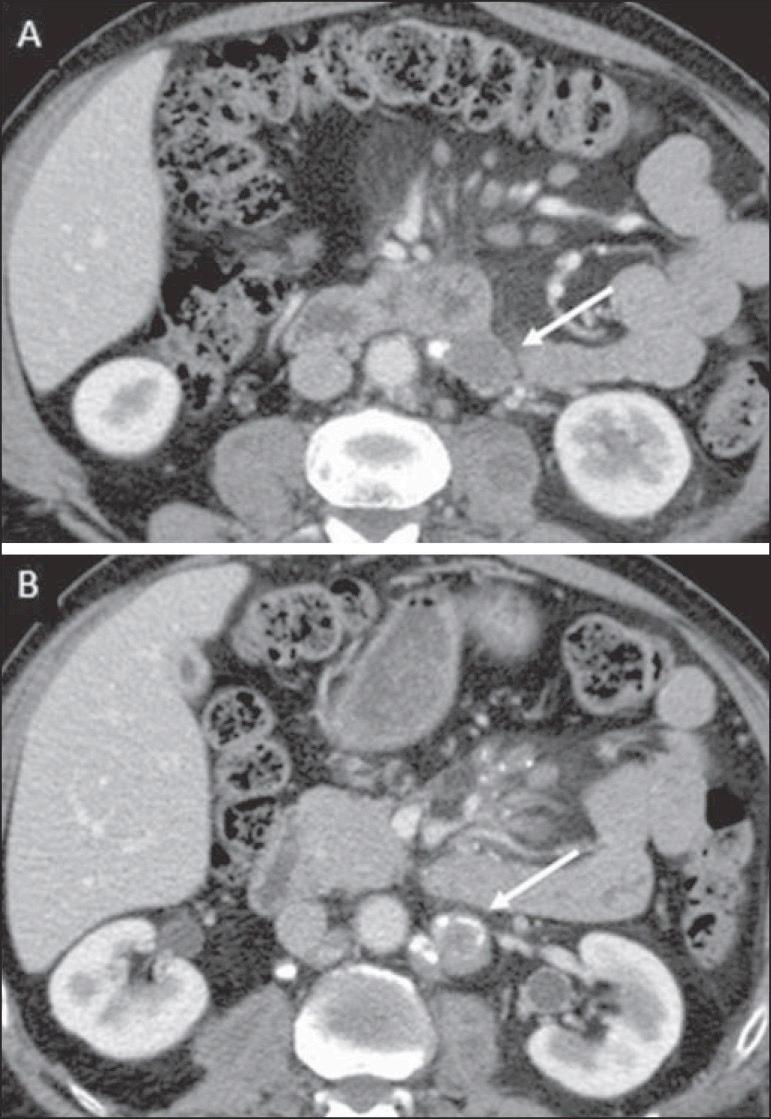

C.4. TB milier

TB milier merupakan penyebaran hematogen luas yang menimbulkan banyak nodul kecil bilateral pada paru dan keterlibatan multi-organ (hati, lien, sumsum tulang, meninges).

Biasanya berasal dari masuknya MTB ke sirkulasi melalui ruptur lesi kaseosa ke pembuluh darah atau drainase limfatik ke duktus torasikus lalu ke sistemik. Gambaran klinis dapat nonspesifik (demam panjang, penurunan BB, hepatosplenomegali) dan memerlukan kewaspadaan tinggi.

Gambar 5: Patologi TB Miliar (Sharma et al,2005)